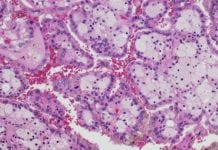

Using AI to determine kidney disease damage

Researchers have utilised artificial Intelligence (AI) to help determine the extent of the damage caused by chronic kidney disease in patients.

A team of researchers...